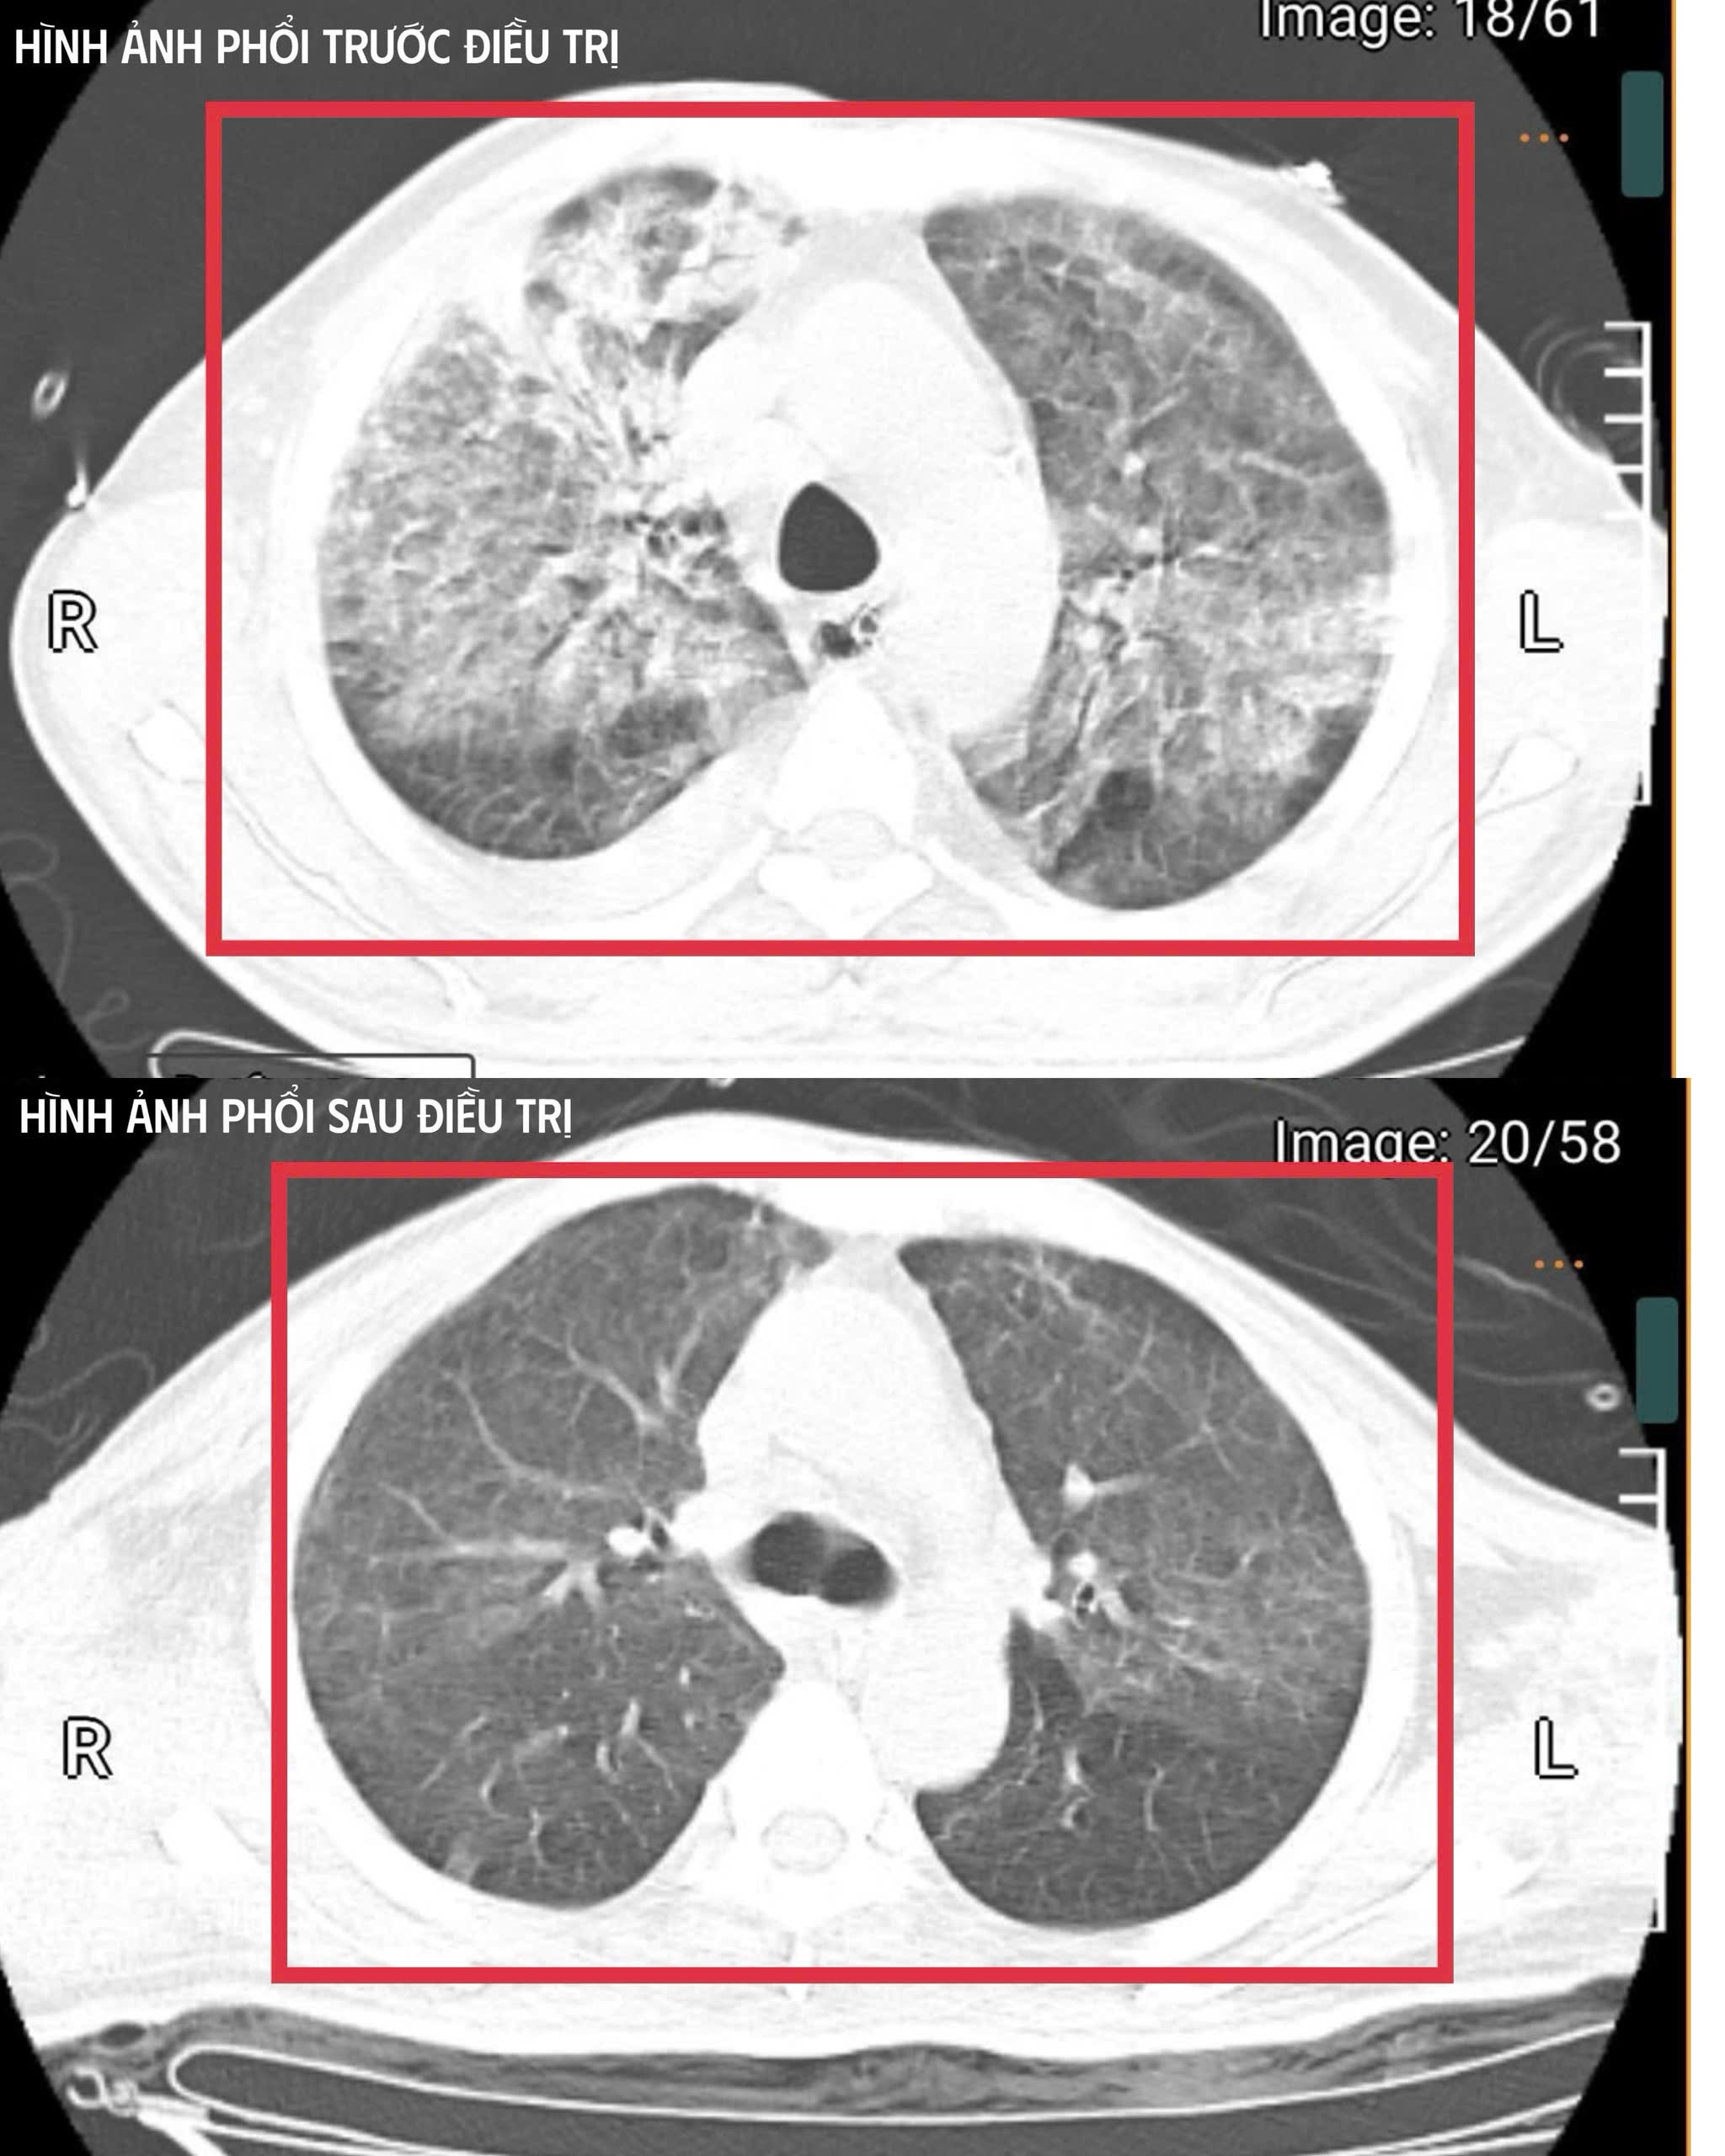

(CLO) Sau khi trở về từ Thái Lan, bệnh nhân 35 tuổi (quê Nghệ An) đã nhiễm vi khuẩn Burkholderia pseudomallei (tác nhân gây bệnh Whitmore, thường được gọi là “vi khuẩn tử thần”) và có diễn tiến tối cấp, suy đa tạng nặng, nguy cơ tử vong rất cao.